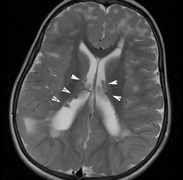

Mental retardation and seizures in TSC are often associated with benign CNS astrocytic hamartomas.131 On imaging, the cerebral lesions show three patterns:132

1. Superficial cortical sclerosis (parenchymal hamartoma) which distort the gyri. Microscopy shows large atypical fibrillary type astrocytes with few associated neurons and areas of calcification.133 The numerous abnormal glial processes and fibers make the tissue abnormally firm or “sclerotic” on palpation (Fig. 13).132

2. Subependymal nodules (SEN) are typically found along the lateral borders of the ventricles and parehncymal brain lesion (“cortical tubers”) (Figs. 14 and 15). Calcification in the first year of life is rare.132

3. White matter abnormalities are a characteristic “ventriculofugal” pattern corresponding to the embryological migratory paths of neurons and glia. These lesions may represent aberrant neuronal migration, a possible reflection of haploinsufficiency for the TSC gene.116,132,134

On MRI imaging, the subependymal nodules and parenchymal brain lesions of infants (age ≤3 months) and adults show different signal characteristics. Infant CNS tubers are hyperintense on T1-weighted images and hypointense on T2-weighted images, which is the opposite of the pattern seen in adults.134 Malignant transformation of SEN occurs in about 10% to 15% of patients and the resultant subependymal giant cell astrocytoma accounts for 25% of premature deaths in TSC.135,136

Fig. 14. Tuberous Sclerosis Complex: Sub-Ependymal nodules. These are typically found along the lateral borders of the ventricles.132

Fig. 15. Tuberous Sclerosis Complex. (a) Patient 1: Axial CT scans demonstrating typical calcification of subependymal nodules in a 13-year-old girl with a history of seizures. (b and c) Patient 2. (b) Axial T2-weighted images demonstrate calcified subependymal nodules (arrowheads) and cortical tubers typical of tuberous sclerosis. (c) Widespread cortical tubers are seen on a coronal FLAIR sequence as thickening of the cortex and high signal of the subcortical white matter.